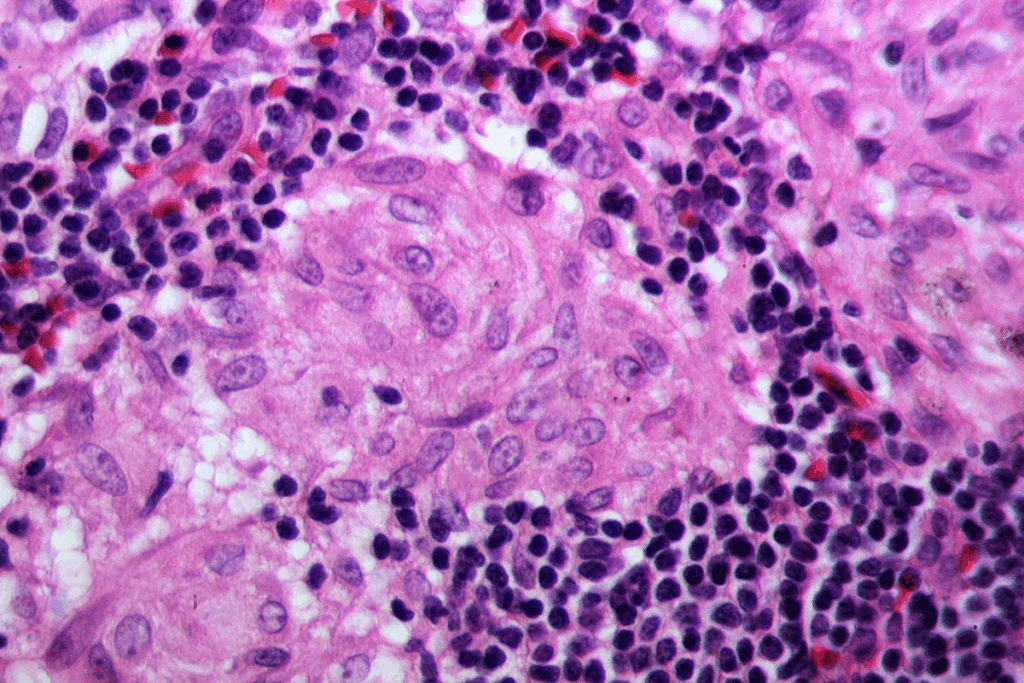

Buccal Mucosa Epithelium: Structure and Composition

The epithelium of the buccal mucosa is unique in its composition and thickness. It acts as a protective barrier in the oral cavity. We will dive into its structure and composition, highlighting its role in oral health.

Stratified Squamous Nonkeratinized Epithelium

The buccal mucosa epithelium is a type of stratified squamous nonkeratinized epithelium. It has multiple layers of cells, with the top layer being flat but not hard. This makes the buccal mucosa flexible and strong, adapting to the oral cavity’s changes.

The buccal epithelium has a dense and regular papillary body of connective tissue. This supports its structure and function. Its thickness and composition show its vital role in oral health.